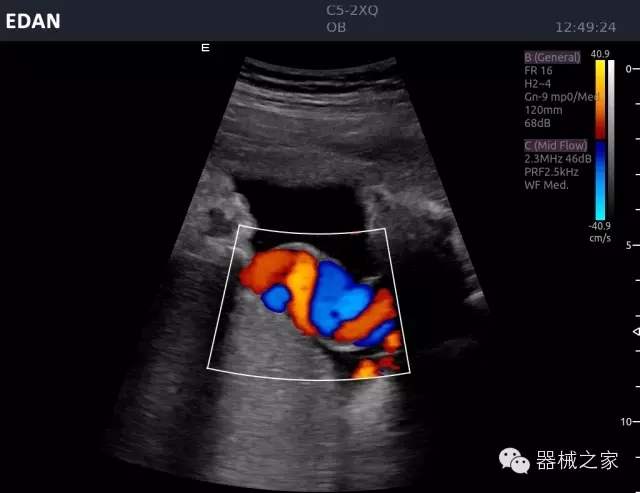

臨床圖片賞析

睪丸低速血流

臍帶血流

頸動(dòng)脈頻譜